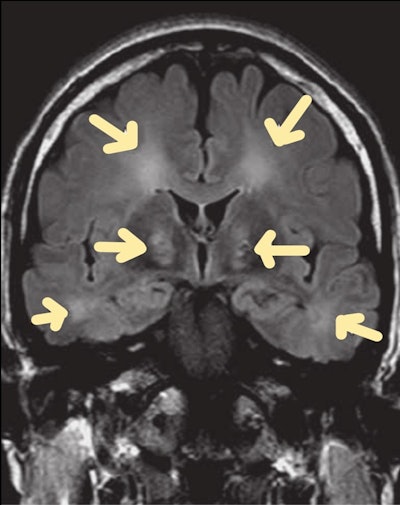

Carbon monoxide (CO) poisoning

CO poisoning can have an impact on the central nervous system and the cardiovascular system. Neurological symptoms resulting from acute CO poisoning range from a minor headache to a coma and possibly death. For most patients, these symptoms can be alleviated with oxygen inhalation or hyperbaric oxygenation. Even a year after CO poisoning, very few people experience long-term neurological symptoms as a result of delayed encephalopathy.

Carbon monoxide poisoning. Brain MRI scan (coronal FLAIR sequence) shows symmetric hyperintense foci in the globus pallidus.

Acute CO poisoning should be diagnosed and detected as soon as possible. In the absence of a history of CO exposure, early detection and diagnosis of CO poisoning can be challenging due to a lack of pathognomonic signs or symptoms.

"The delayed symptoms of CO poisoning result from the inhibition of the mitochondrial electron transport enzyme system by CO and the activation of polymorphonuclear leukocytes, which produce brain lipid peroxidation and diapedesis," the authors wrote.

In these patients, CT shows low attenuation in the globus pallidus. On MRI, the medial portions of the globus pallidus appear as bilateral areas of low signal intensity on T1-weighted images and of high signal intensity on T2-weighted and FLAIR images. The degree of carboxyhemoglobin and the range or intensity of MRI results do not appear to be related.